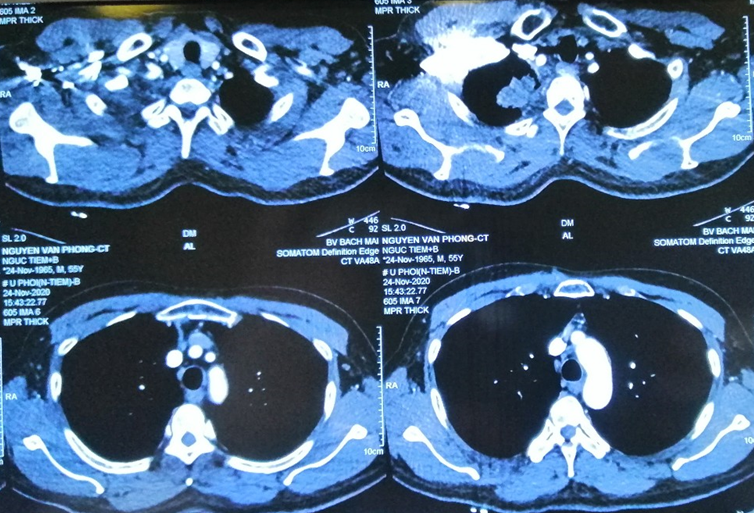

– Chụp cắt lớp vi tính lồng ngực:

Hình 1: Hình ảnh chụp cắt lớp vi tính lồng ngực: Hình ảnh khối u thùy trên phổi phải kích thước 5x6cm, hạch trung thất, rải rác tổn thương thứ phát hai phổi (Mũi tên màu đỏ).